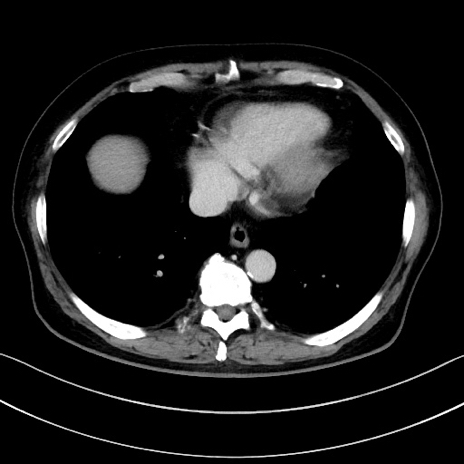

冠状断像

【症例】70歳代男性

【主訴】腹痛

【現病歴】今朝から腹痛あり。全体的に痛い。特に左上の方。排ガスが今日はない。冷や汗が出る。

【既往歴】直腸癌術後

【身体所見】左側腹部〜上腹部に圧痛あり。腹膜刺激症状明らかなではない。軽度反跳痛。左下腹部に術後瘢痕あり。

【データ】WBC 7700、CRP 0.02